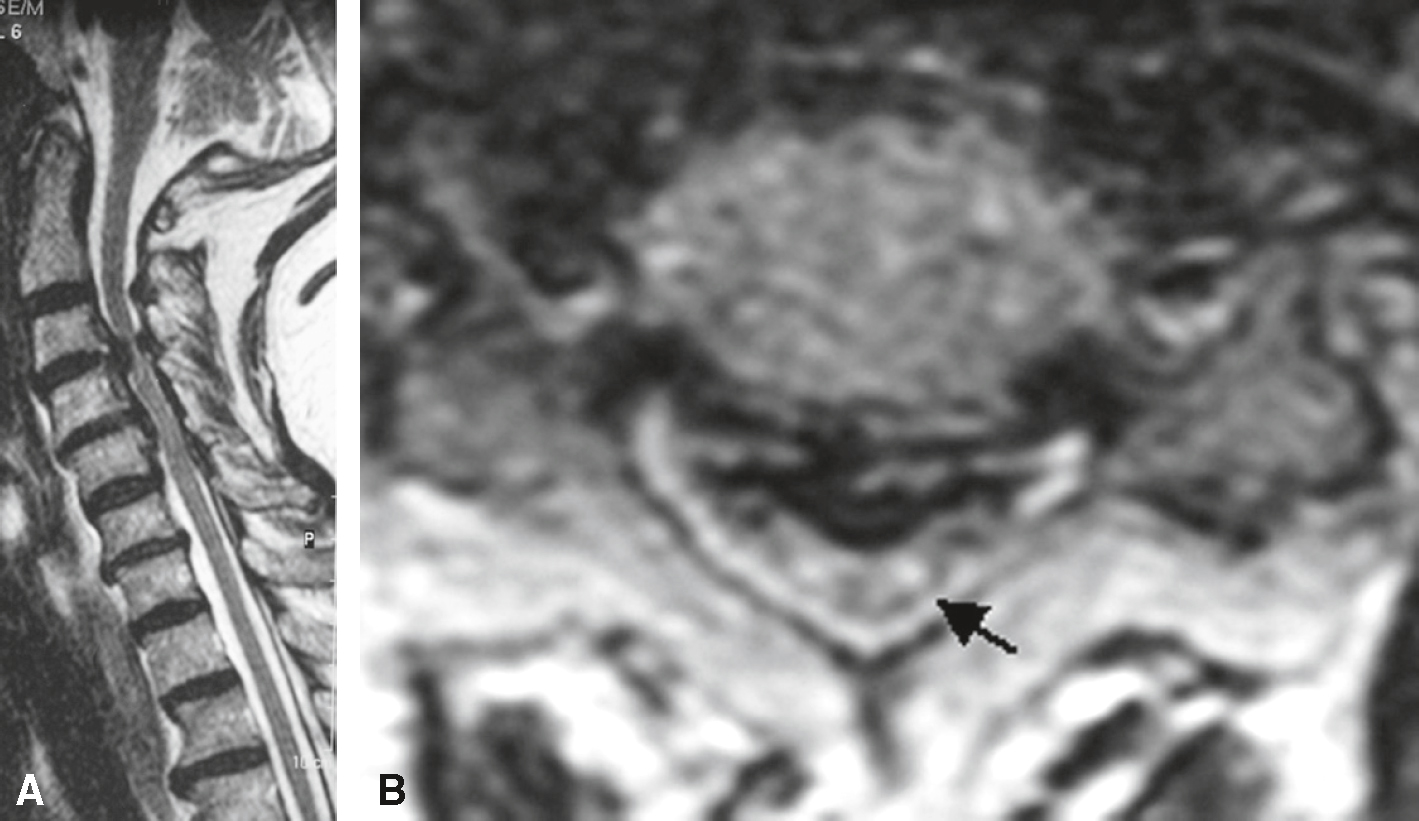

Fig. 7.4

Myélopathie cervicarthrosique.

Sténose du canal cervical en C4-C4 et en C4-C5, d’origine dégénérative avec éperons osseux antérieur et postérieur en C3-C4 en hyposignal (grande flèche). Les espaces liquidiens périmédullaires sont effacés sur deux étages et la moelle est laminée. Il existe un hypersignal intramédullaire en regard de l’interligne C3-C4 témoignant d’une souffrance ischémique liée à la compression chronique de la moelle. A. T2 sagittal. B. T2 axial.Cette image IRM en deux plans illustre une myélopathie cervicarthrosique. L’image A correspond à une coupe sagittale médullaire, montrant une réduction marquée du canal rachidien cervical avec un aplatissement de la moelle épinière au niveau de plusieurs étages cervicaux, notamment à mi-hauteur. On y observe une hyperintensité intramédullaire en hypersignal T2, suggérant une souffrance médullaire chronique par compression. L’image B, en coupe axiale, met en évidence un rétrécissement concentrique du canal rachidien et un débord discal postérieur associé à une hypertrophie des articulations zygapophysaires. La flèche noire pointe une zone de compression directe de la moelle au centre du canal cervical. Cet aspect est typique des lésions dégénératives chroniques responsables de signes cliniques tels que troubles de la marche, paresthésies ou faiblesse des membres supérieurs.